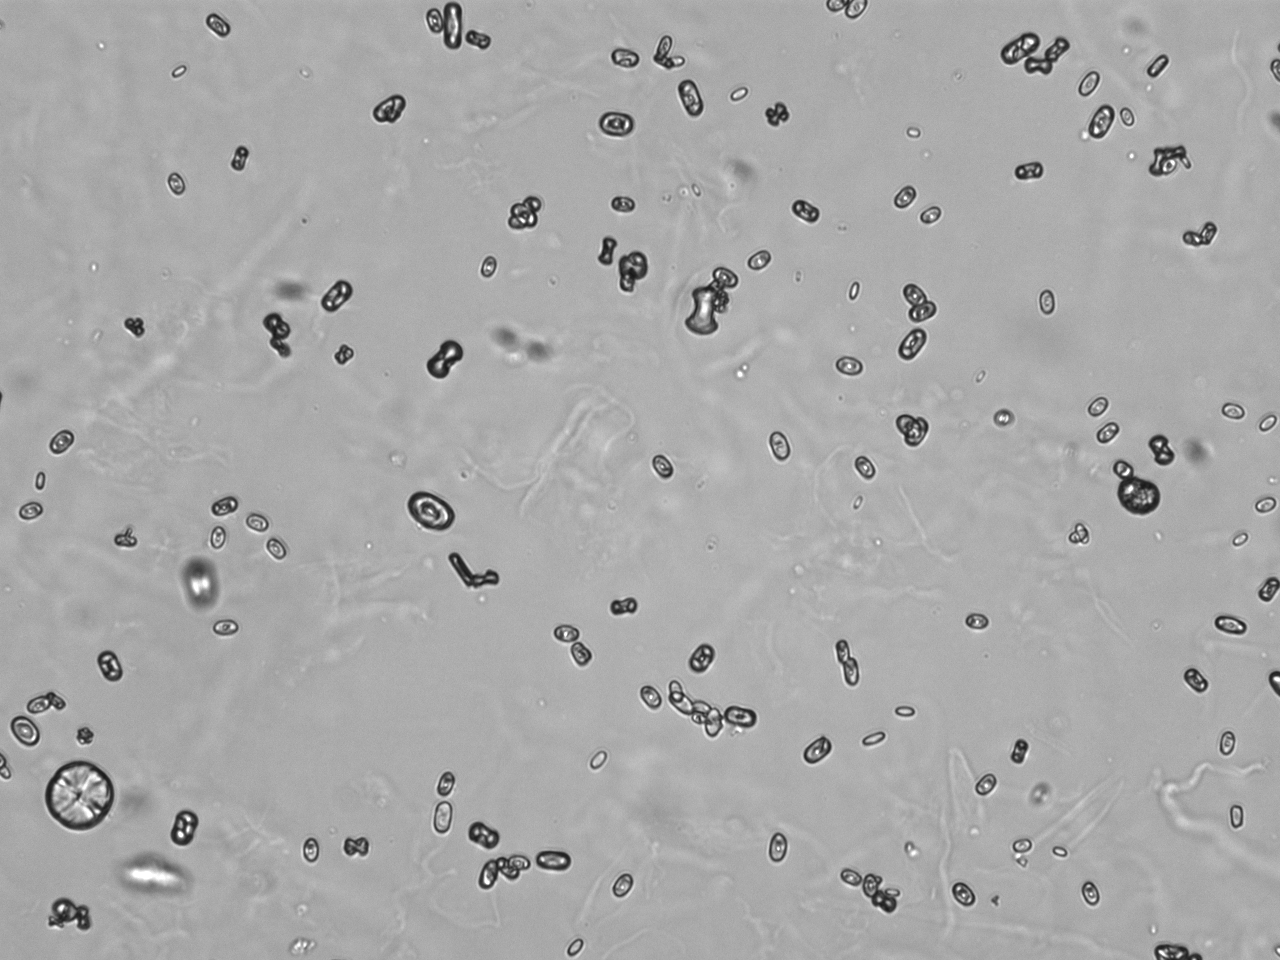

Urin-Feature: CaOxalateMonohyd